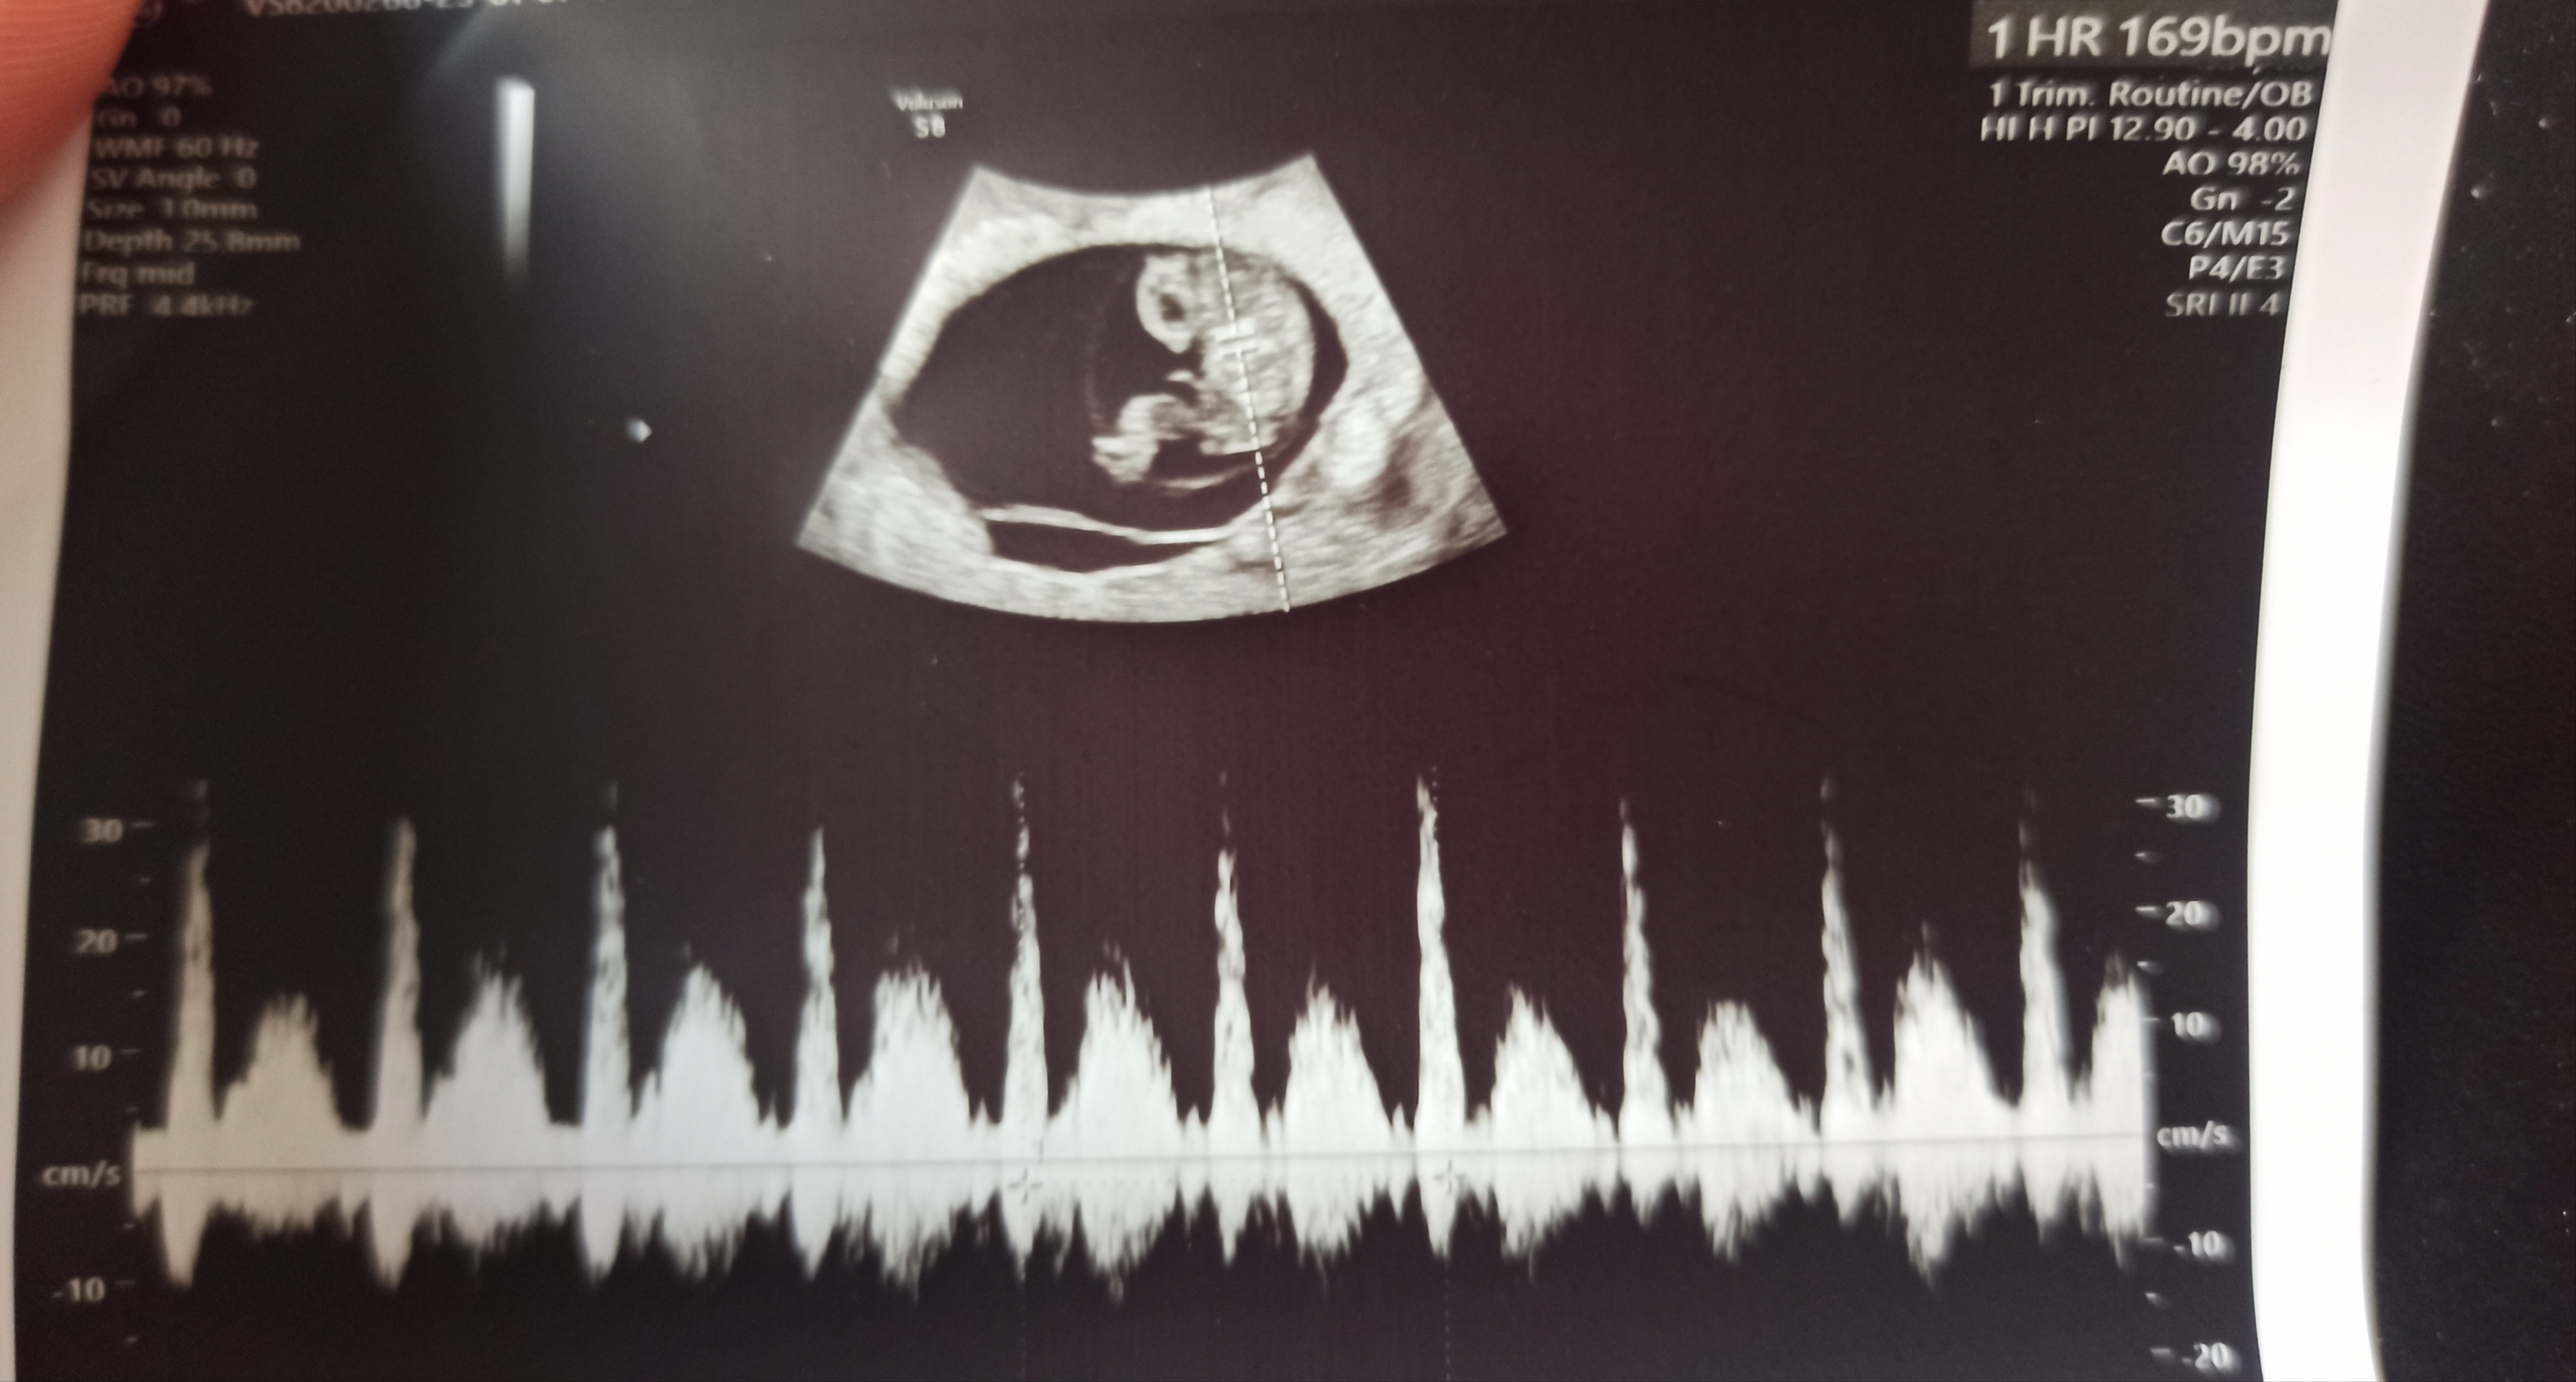

Już po wizycie, wszystko dobrze, mała dzidzi rośnie, jest teraz 8+1, mierzy 1.69cm. Karta ciąży zalozona, muszę się teraz na pappa umówić. A dziś mi strasznie niedobrze, ledwo doszłam do tej lekarki.

A tu jest jeszcze z innego kątaPiękniejszego małego człowieka jeszcze nie widziałam![]()